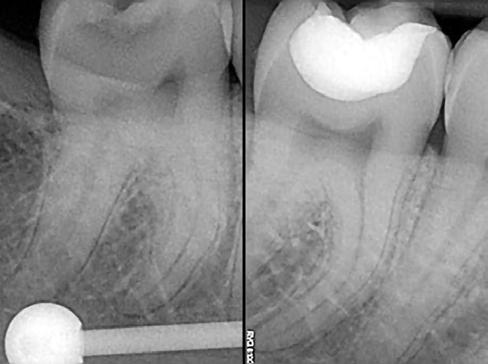

A kiindulási és a posztoperatív röntgenfelvétel segítségével jól meg lehet ítélni az elkészült tömés minőségét (31. ábra).

A thermo-viszkózus kompozit tömőanyag kiváló anyagtani tulajdonságainak köszönhetően nem maradtak vissza légzárványok a tömőanyag rétegei között. A tömés elkészítése során felhasznált három különböző tömőanyag radioopacitása megegyezik, és az egész tömés egy homogén blokknak tűnik a felvételen. Nem látható az átmenet az alaptömésként használt folyékony kompozit, a bulk-fill kompozit és az esztétikus kompozit között.

A kiindulási röntgenfelvétel alapján nem lehetett pontosan megítélni a szuvas lézió mélységét. Csupán a szuvasság feltárását követően vált nyilvánvalóvá, hogy egy rendkívül mélyre terjedő szuvassággal állunk szemben. Ennek megfelelően az üregalakítás befejezésekor már csak egy vékony réteg ép foganyag választotta el a fogbelet a külvilágtól, amely miatt fontos volt az üreg pulpális falainak védőlakkal való fedése.